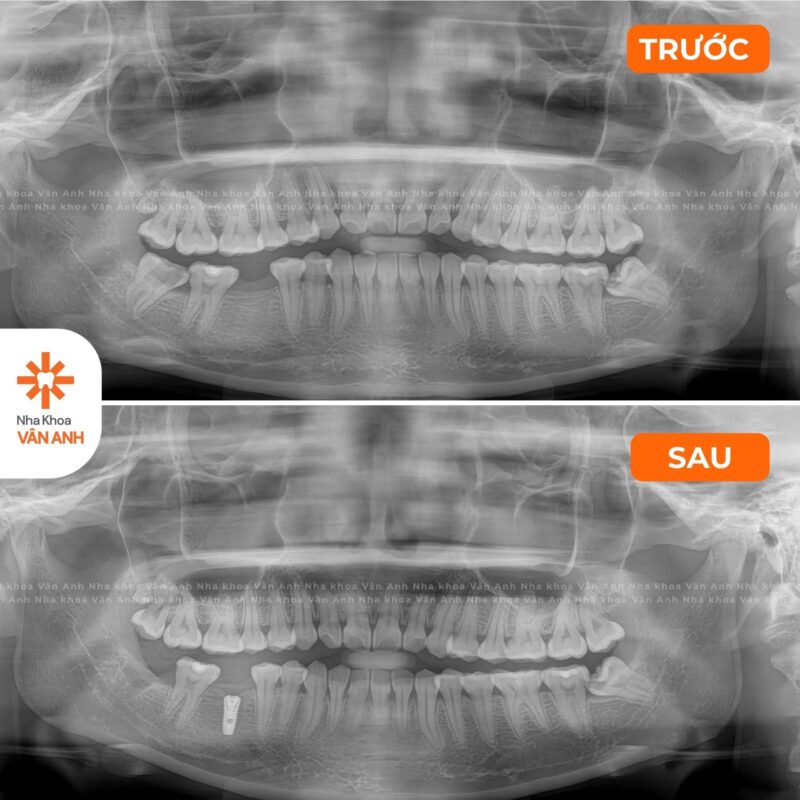

Lĩnh vực chuyên sâu: Phục Hình – Tiểu Phẫu

- Chứng chỉ Cắm Ghép Implant Nha Khoa – Viện Đào tạo Răng Hàm Mặt, Đại học Y Hà Nội.

- Chứng nhận đào tạo Cấy ghép implant Nha khoa nâng cao: Implant tức thì và Implant vùng thẩm mỹ – Viện Đào tạo Răng Hàm Mặt, Đại học Y Hà Nội.